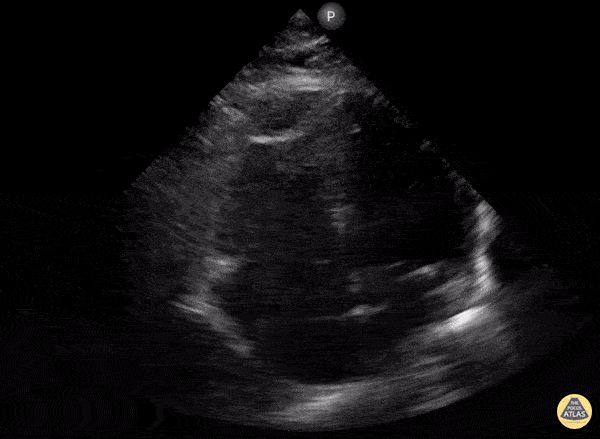

A 56-year-old with metastatic cancer presents with progressive dyspnea, chest discomfort, and fatigue. Vitals: HR 128, BP 84/56, RR 28, SpO₂ 93% RA. Exam: ill-appearing, elevated JVP, muffled heart sounds, cool extremities, clear lungs. A focused apical 4-chamber cardiac PoCUS image is shown.

What are the key ultrasound findings? What is the most likely diagnosis?

Findings: large pericardial effusion

Diagnosis: What is cardiac tamponade?